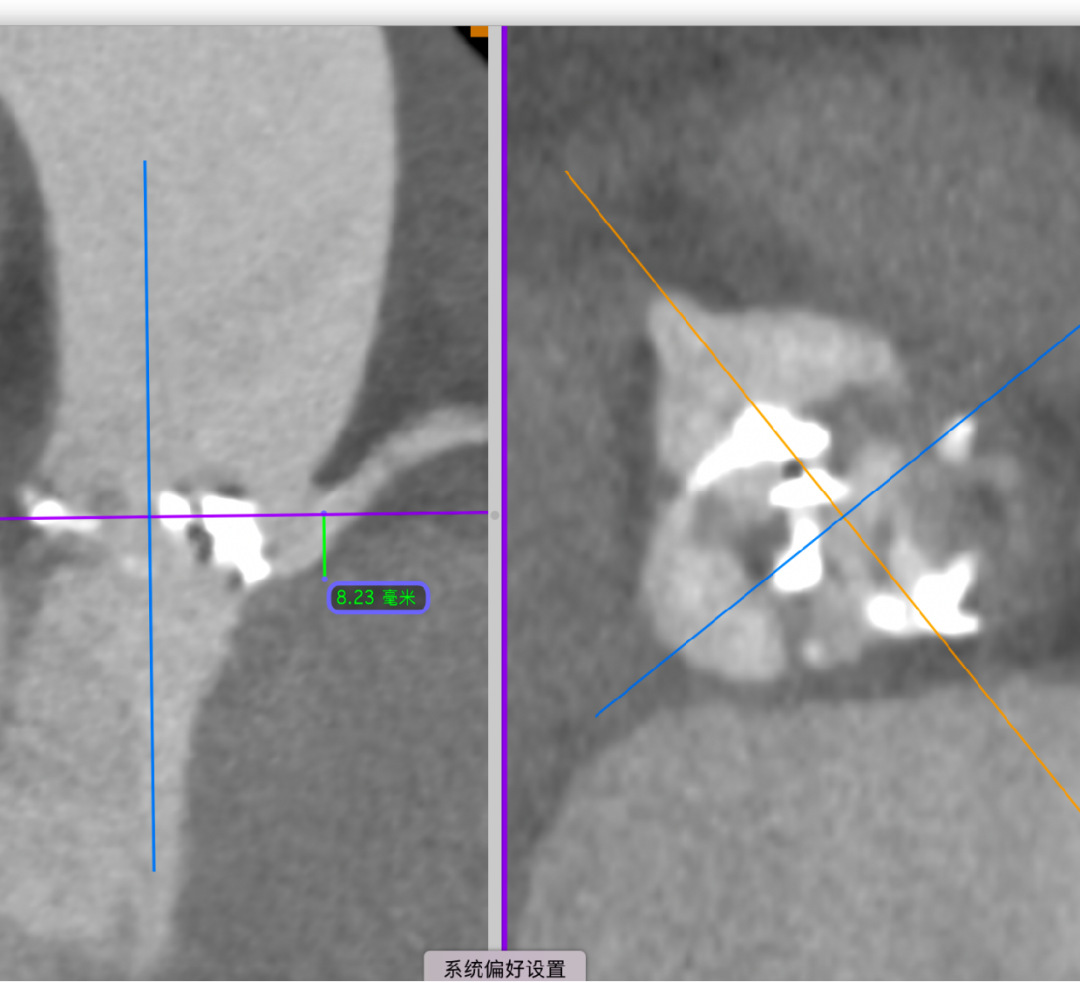

主动脉根部CT断层

根部角度/瓣环/左室流出道

瓣上结构2,4,6,8,10,12mm

SOV/STJ/AAO

左冠风险评估

间隔膜部